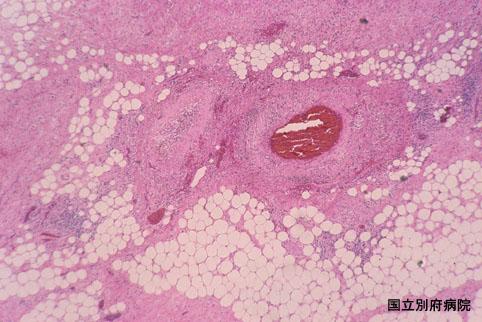

A case of ischemic colitis on hypereosinophilic syndrome mimicking colon cancer.

Oita Pref., National Hospital Organization Beppu Medical Center

Inflammatory or ulcerative disease / lesions/Ischemic colitis

Large intestine(Colon)/Ascending colon

Histology